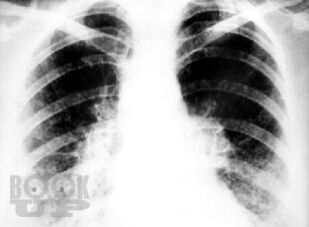

В монографии на современном научном уровне изложены вопросы истории изучения саркоидоза, представлены вопросы его этиологии, патогенеза, а также эпидемиологические, морфологические, клинические и функциональные аспекты его проявления. Авторами разработаны и внедрены в практику простые, повсеместно доступные, высокоинформативные и интегральные новые диагностические критерии оценки состояния гомеостаза у больных саркоидозом на основе оценки состояния и динамики гематологических показателей. Корректировка показателей гомеостаза (типов адаптационных реакций организма, типов реактивности организма, лейкоцито-лимфоцитарного индекса, показателей энтропии и избыточности форменных элементов белой крови и показателей белковых фракций крови) позволила внедрить в практическую работу математические модели и графики факторных пространств для проведения персонифицированного назначения активаторов защитных систем организма, контроля активационной патогенетической терапии и повысить эффективность лечения саркоидоза.

Монография может быть полезна для врачей-терапевтов, пульмонологов, рентгенологов, дерматологов, а также для врачей-интернов различных специальностей, клинических ординаторов и студентов старших курсов медицинских вузов.